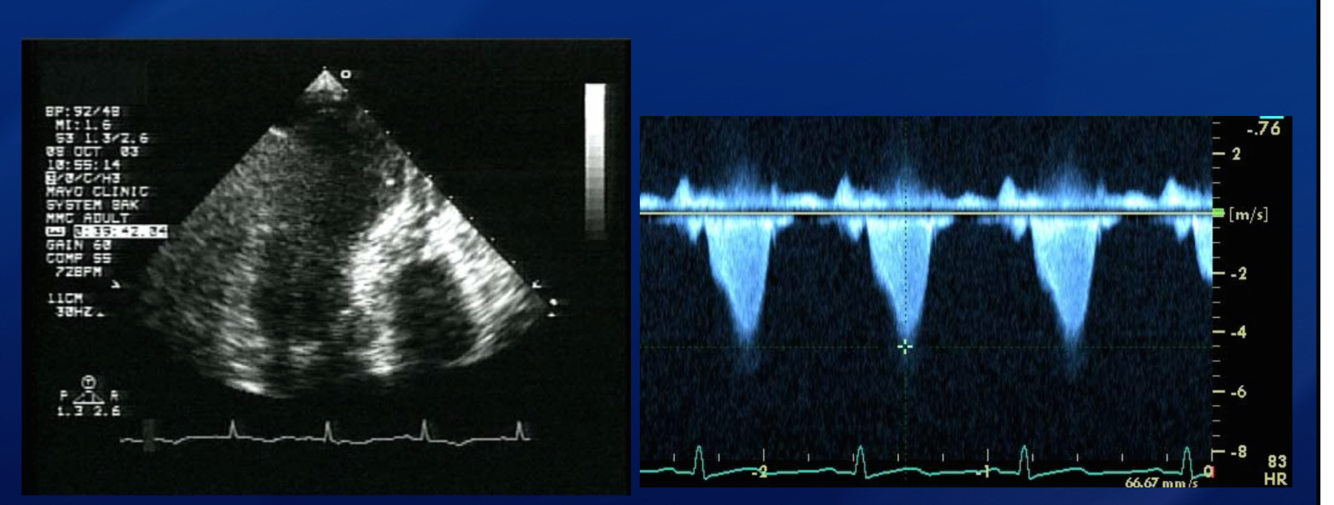

Shock and murmur after AWMI. Diagnosis?

Dynamic LVOT obstruction